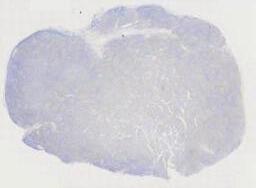

第五例 “一例少见的淋巴结病变” 男/66岁,左颈部淋巴结。

临床资料:   男,66岁,主诉:水肿、颈部淋巴结肿大,同期发现房颤。现病史:2020-05出现心悸伴颜面部、颈部、四肢水肿,尿量减少(约500ml/d),咳嗽、喘憋、活动耐量明显下降。外院完善ECG:“房颤”,颈部超声:双侧颈部淋巴结肿大。2020-06我院查:血常规:(-),肝肾功:LD365U/L,余(-);心肌酶(-);NT-proBNP1465pg/ml;感染:HBcAb(+),HBsAb(+);ECHO:LVEF69%,左房增大,心包少量积液。PET-CT示:1.左侧颈部(IV区、V区)、左侧锁骨上下、右肺门及后纵隔、腹膜后、肠系膜上多发代谢增高淋巴结(大小约0.5-1.6cm,SUVamx13.2),右心房、右心室及双侧心耳见多发代谢增高结节和肿物(大小约2.0×2.3-5.8×7.6cm,SUVamx24.6)、第2/3组小肠壁明显增厚且代谢增高异常(SUVamx17.1)。取左颈根部淋巴结送检。

大体所见:   淋巴结样组织数枚,直径0.5-2cm。